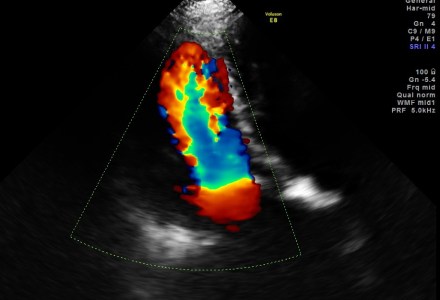

Candle flame sign in mitral stenosis